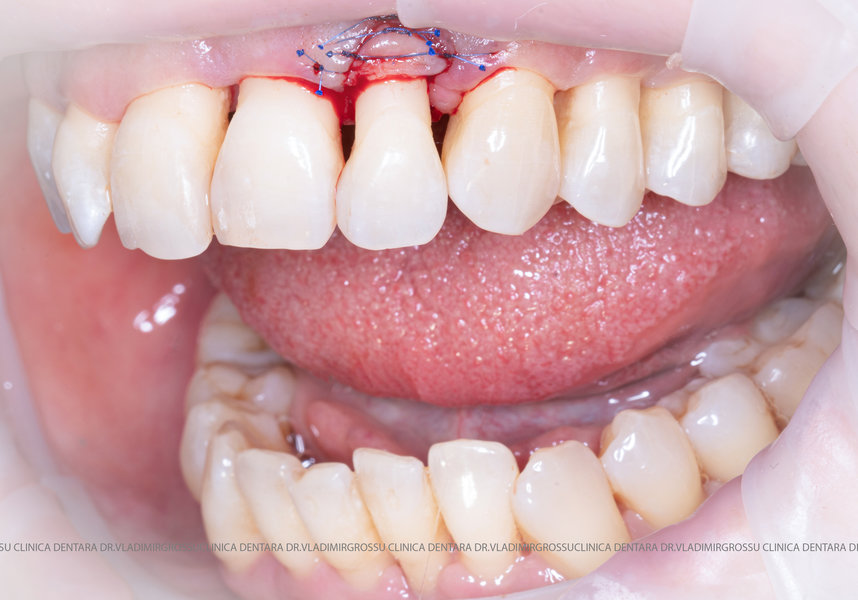

Adiția de gingie (gingivoplastia)

Aditia gingivală este o procedură chirurgicală ce corectează diverse probleme estetice și funcționale, cum ar fi recesiunea gingivală. În implantologia modernă, aditia de țesut moale este utilizată aproape în fiecare intervenție de inserție a implantului dentar pentru a asigura un aspect estetic natural și o bună integrare a implantului în cavitatea bucală.